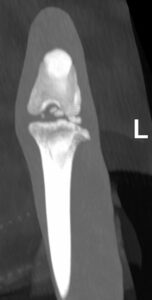

X-ray – Left Stifle

Diagnostics: Odysseus was admitted for CT and joint taps under general anaesthesia. He was sedated with the owner to reduce the stress associated with the procedure. On CT, he had bilateral intra-articular lesions possibly associated with a cranial cruciate ligament disease and historic fractures of his right metatarsals with callus formation. There were some mild osteoarthritic changes in some joints but his spine was normal. Joint taps showed changes that could indicate IMPA but this was not definitive.